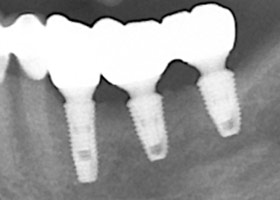

9. 治療後,X光片。

![proimages/save-defeat05-2.jpg proimages/save-defeat05-2.jpg]()